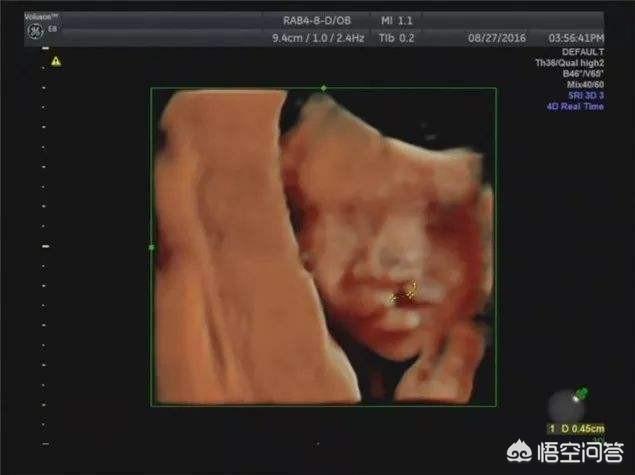

B超音波検査は一般的に胎児の発育と胎盤の位置をチェックするもので、胎児の病気の問題に関わることはほとんどありません。 4D超音波検査だけが胎児の奇形をスクリーニングするものなので、あなたが質問しているのはB超音波検査ではなく4D超音波検査のはずです。

4D超音波検査は、Bスキャン超音波検査の拡張版であり、胎児の奇形、胎児の顔や体の器官、四肢の奇形、例えば、胎児の口唇裂、合指症、四心室、内臓外反などを検出することができる。

妊娠中の4D超音波検査は、胎児の先天性心疾患、水頭症、口唇口蓋裂、四肢の発育をチェックすることができます。4D超音波検査では、母体内の胎児の動く画像も見ることができる。

一般に3D超音波検査または4D超音波検査と呼ばれるこの検査は、胎児の様々な器官や臓器に先天性疾患がないかを調べるための超音波検査である。

超音波(4D超音波)は妊娠検査に必要なもので、主に胎児の体表や様々な臓器に奇形がないかをスクリーニングする役割を担っています。例えば、胎児の心臓、脳、腎臓、その他の部分の病気などです。

近年人気の超音波検査法である4D超音波検査を挙げる回答が多かった。 胎児の姿をより鮮明に見ることができ、母親や父親になる人に喜びや楽しみを与えるだけでなく、ビデオや写真を記録して記念に残すこともできる。